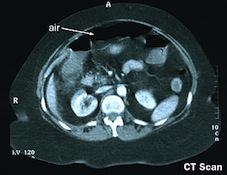

La radiographie de l’abdomen sans préparation reste surtout indispensable pour éliminer un pneumopéritoine par perforation d'un ulcère sous la forme d'un croissant gazeux sous-diaphragmatique (Figure n°1).

Figure n°1 et 2 : Pneumopéritoine sur un ASP de face et sur une tomodensitométrie.

La tomodensitométrie (TDM) abdominale permet de confirmer le pneumopéritoine devant la présence d'air dans le péritoine et peut orienter la localisation de la perforation.

Il est interdit de réaliser dans ce contexte une endoscopie car cet examen ne fera qu'aggraver le pneumopéritoine en introduisant encore plus d'air. Le seul traitement est alors la chirurgie en urgence.